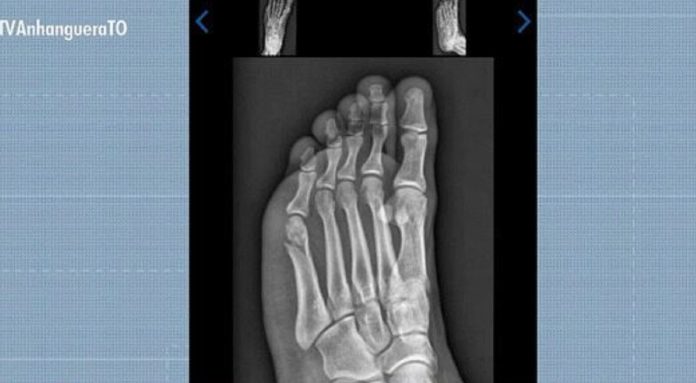

Um jovem concurseiro de Gurupi, no sul do Tocantins, conseguiu ser aprovado no Teste de Aptidão Física (TAF) da Polícia Militar mesmo com o pé quebrado. A prova aconteceu 30 dias após Gabriel Santos Rodrigues, de 22 anos, cair do telhado da própria casa enquanto trocava a boia da caixa d’água.

Gabriel Santos Rodrigues foi aprovado no TAF da PMTO mesmo com fratura no pé

Reprodução/TV Anhanguera